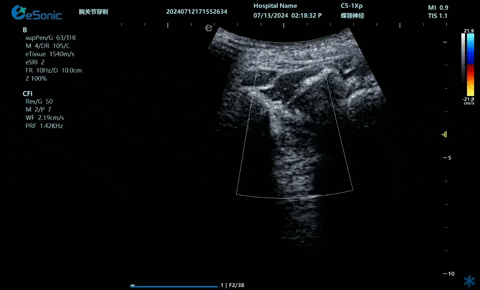

超声引导硬膜外麻醉-小等号

管内麻醉